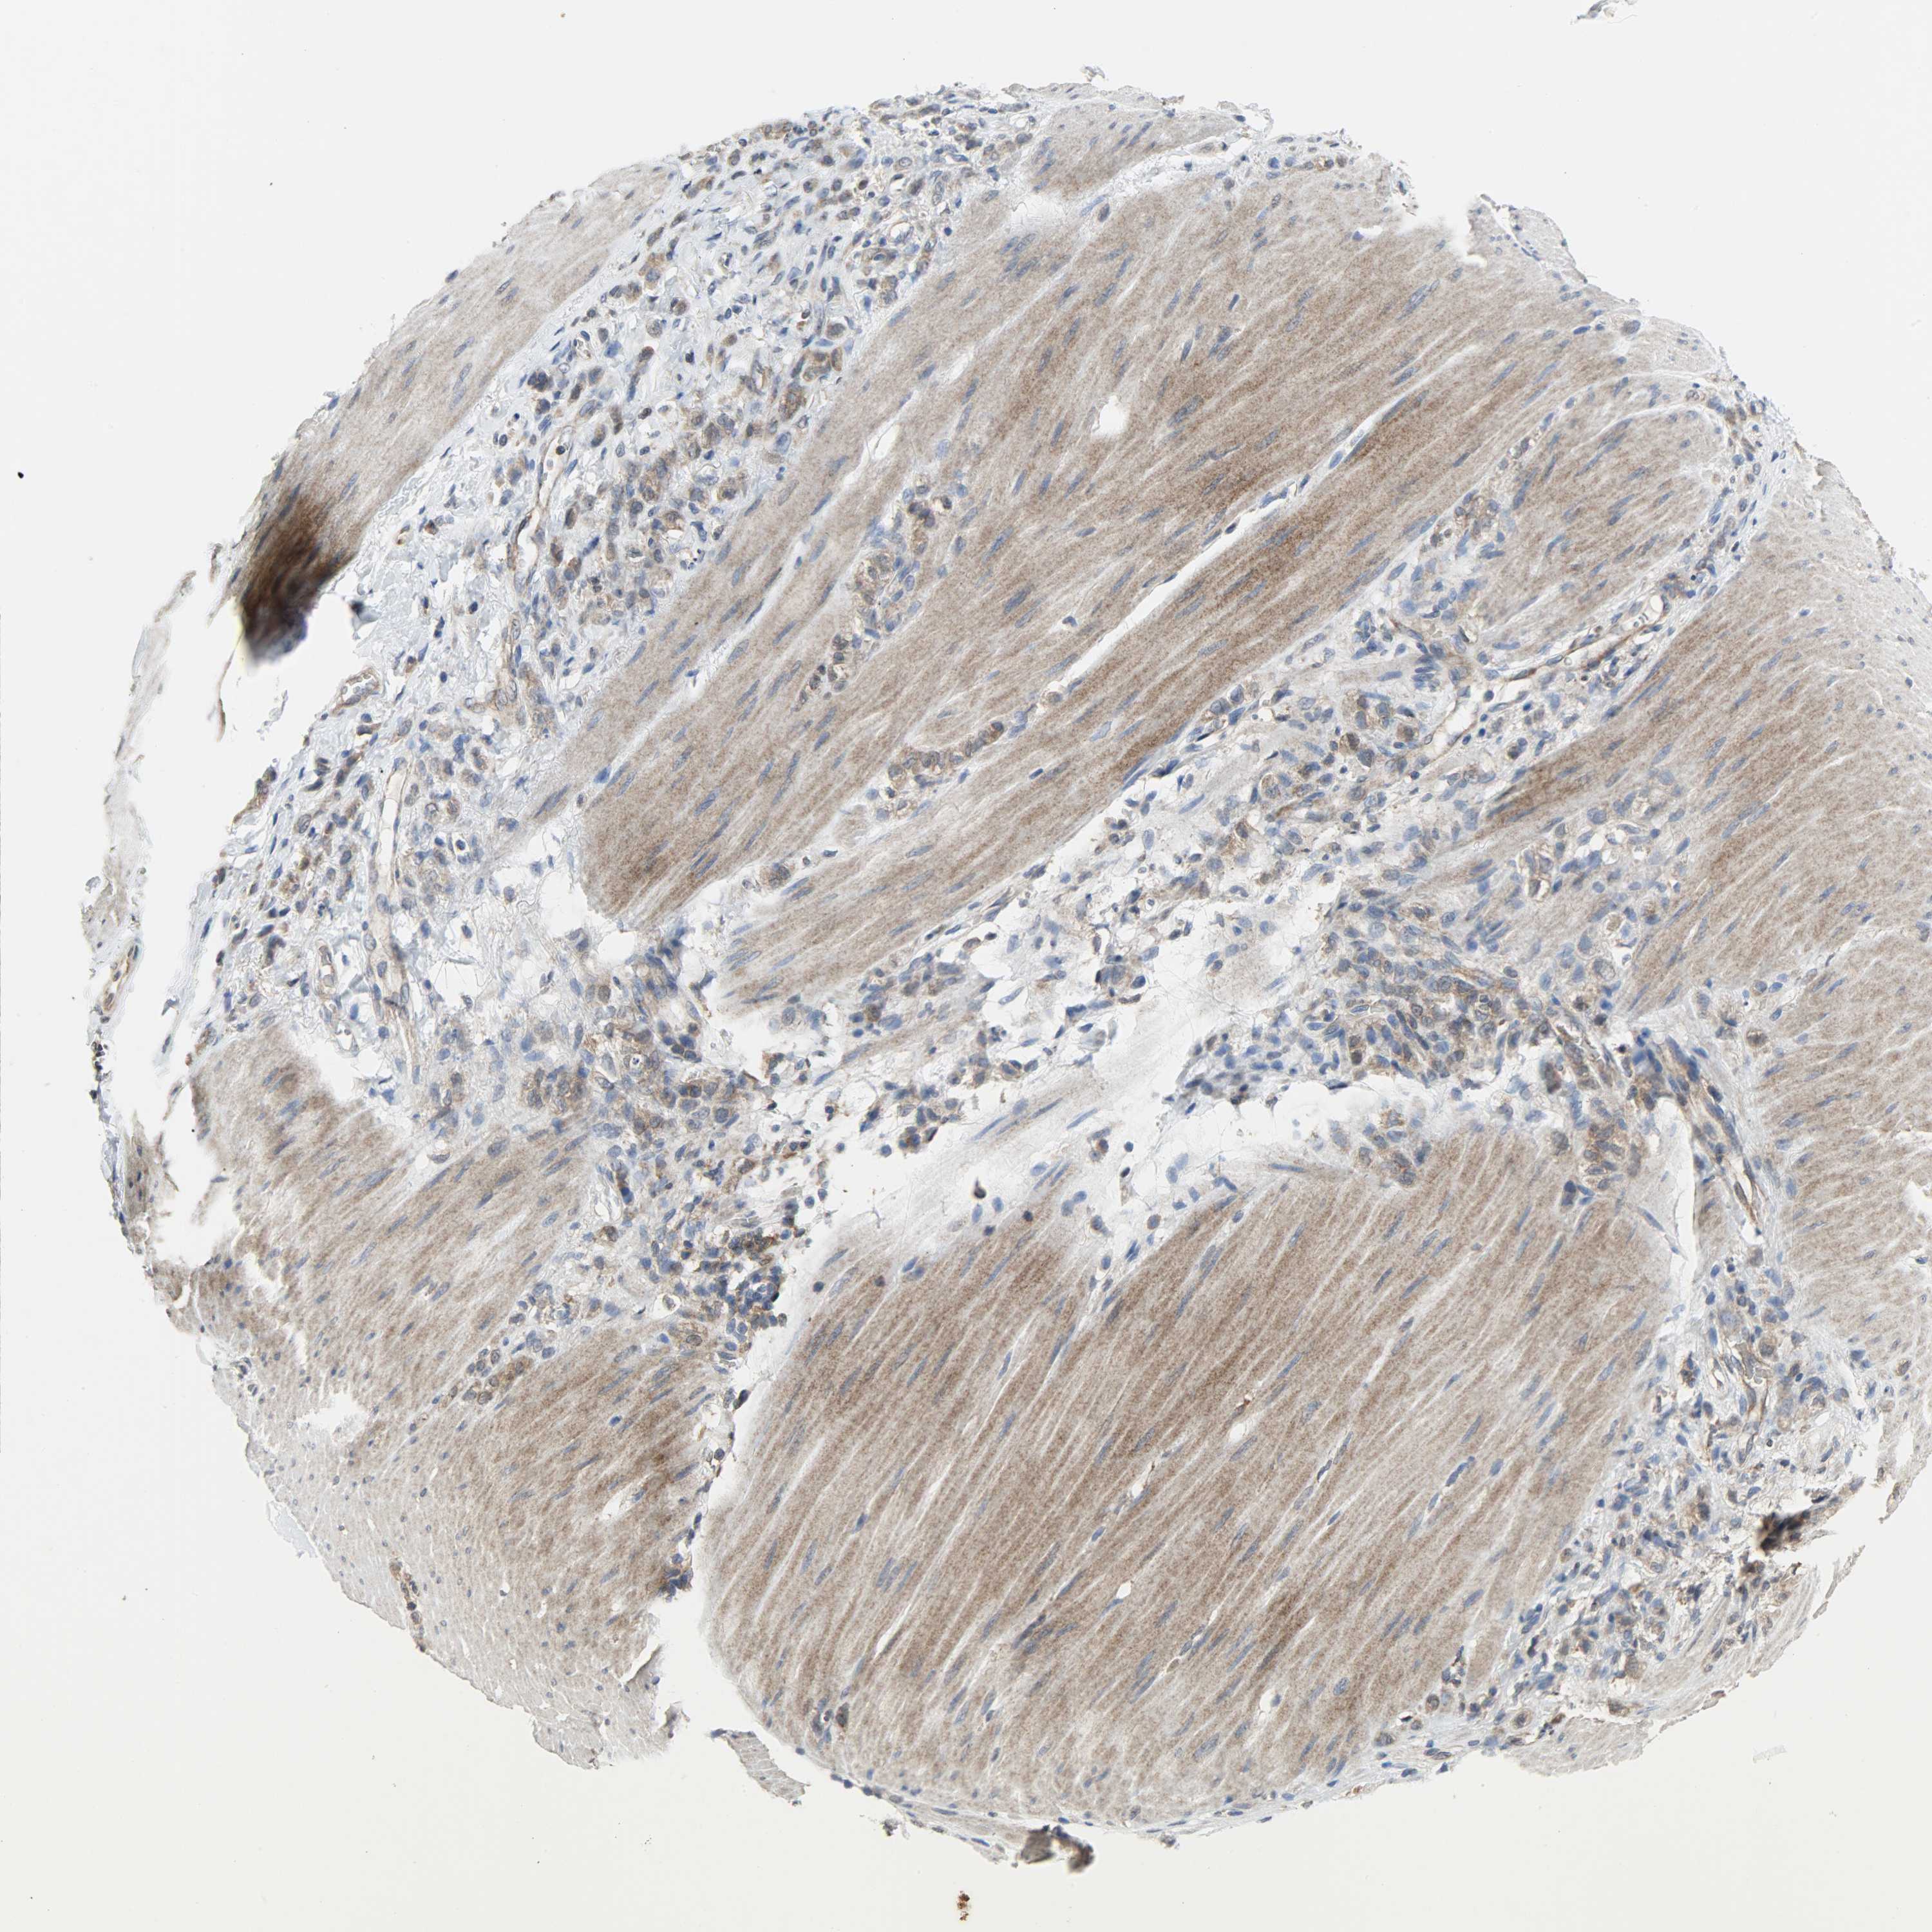

STOMACH CANCER - Protein expressioni

A mouse-over function shows sample information and annotation data. Click on an image to view it in a full screen mode. Samples can be filtered based on level of antibody staining by selecting one or several of the following categories: high, medium, low and not detected. The assay and annotation is described here.

Antibody stainingi

Antibody staining in the annotated cell types in the current human tissue is reported as not detected, low, medium, or high, based on conventional immunohistochemistry profiling in selected tissues. This score is based on the combination of the staining intensity and fraction of stained cells.

Each image is clickable and will lead to virtual microscopy that enables deeper exploration of all samples and also displays staining intensity scores, fraction scores and subcellular localization as well as patient and tissue information for each sample.

Antibody HPA005673

Antibody CAB004566

Staining

High

Medium

Low

Not detected

Intensity

Strong

Moderate

Weak

Negative

Quantity

>75%

75%-25%

<25%

None

Location

Nuclear

Cytoplasmic/membranous

Cytoplasmic/membranous,nuclear

Adenocarcinoma, NOS

Adenocarcinoma, High grade